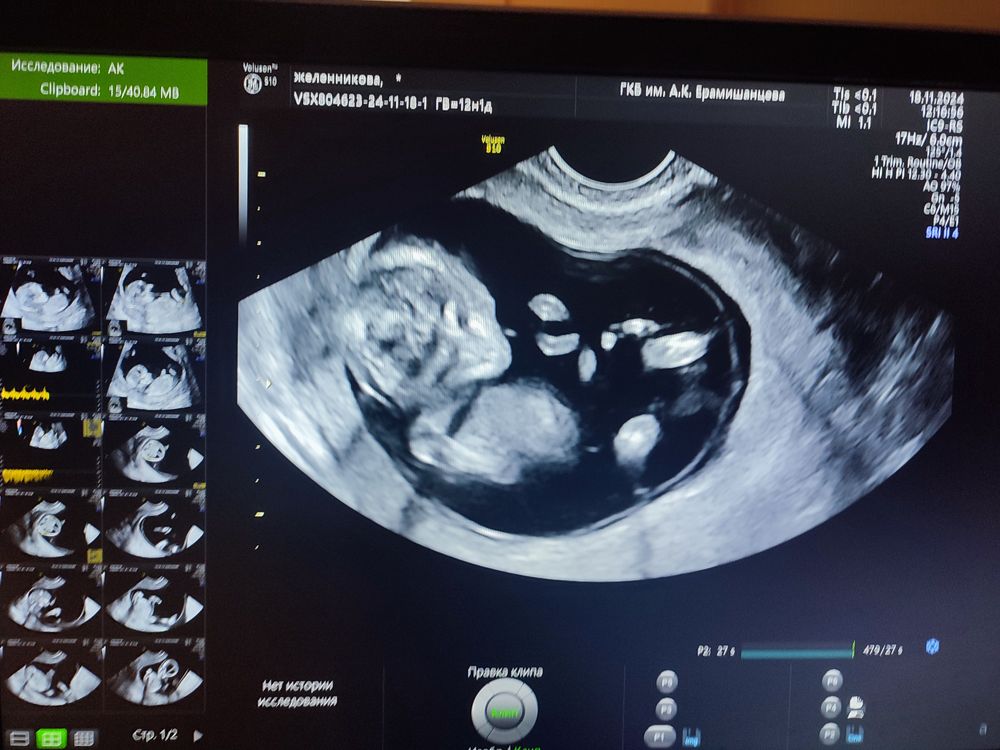

Скрининг. Фуф

Очень рада,Катюш!!! Как время быстро летит, уже первый скрининг 🥹♥️

Энни, да, всё отлично) пришла лежу теперь😂 силы иссякли от переживаний. Сб сегодня 164). Жду ваших результатов). Напишете?

Екатерина, сходила. Чуть не плакала от волнения🙈 малыш наш 69мм, обгоняет срок немного. На 13.1 неделю насчитали. Бпр 20мм, твп 1.4. Сердечко 161. Носовая кость визуализируется🤞 сказали видно, что мальчик😊 но мы и так знали. Она его назвала попрыгунчик )) не давал смотреть нормально) Немного смутили меня ПИ в маточных артериях. Сильно отличаются (0.59 и 1.79), но она ничего про это не сказала. Ждём результатов по крови теперь. А 9.01 второй скрининг. А вам уже назначили или пока нет?